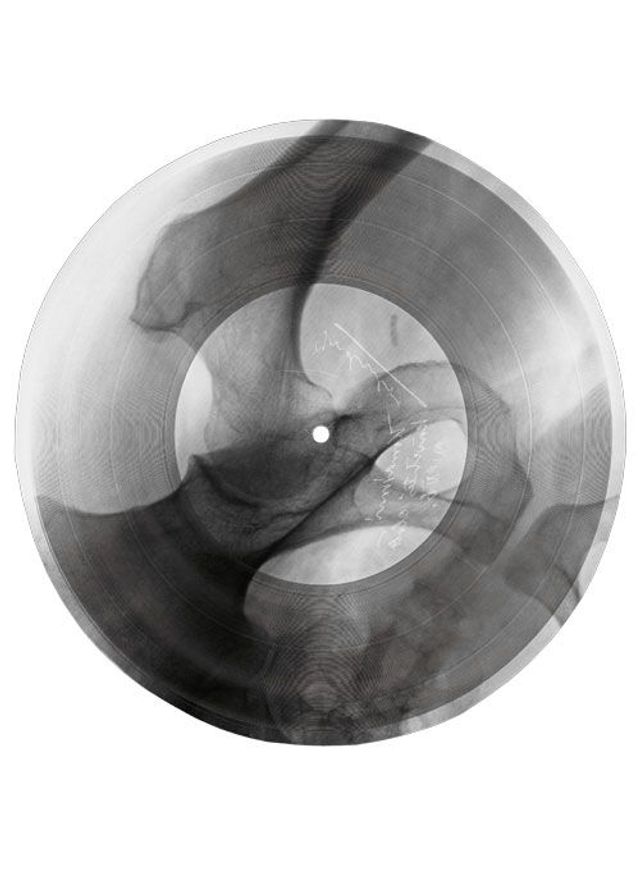

»Was haben wir für einen schönen Abend«, singt Anna Kapitány, während sich die Röntgenaufnahme eines menschlichen Schädels auf dem Grammophon dreht. Musik auf Skeletten – das wäre eine wunderbare Marketing-Idee für eine Black-Metal-Band. Aber zu Kapitánys heiterem Bigband-Swing tanzten die Ungarn in den Dreißiger- und Vierzigerjahren. Diese Lieder wurden live gespielt und im Radio übertragen. Nur für die Ewigkeit ließ sich ihre Musik schwer festhalten: Im Krieg war Schellack selten, das Harz aus den Ausscheidungen der Lackschildlaus musste aus Indien importiert werden. Also suchten Musikliebhaber und Mitarbeiter des ungarischen Radios eine Alternative – und fanden sie in Krankenhäusern.

Die Zelluloidfolien, auf denen gebrochene Rippen, ausgerenkte Gelenke, tuberkulöse Lungen abgebildet wurden, waren gerade dick und haltbar genug, dass man mit einer Plattenschneidemaschine Tanzmusik oder Ansprachen von Politikern hineingravieren konnte. Die biegsamen Platten wurden mal mehr, mal weniger sorgfältig in eine runde Form geschnitten, sodass sie auf den Teller des Grammophons passten. Für die Nadel war es egal, ob sie von Rillen im Schellack oder im Zelluloid zum Schwingen gebracht wurde. Zu lange durfte das Stück nicht dauern – auf eine Scheibe mit 23 bis 25 Zentimetern Durchmesser passten nicht viel mehr als drei Minuten. Ein halbes Jahrhundert zuvor waren die Röntgenstrahlen entdeckt und das Grammophon erfunden worden, nun verschmolzen sie zu einer Technik.

Nach dem Fall des Eisernen Vorhangs hat der ungarische Fotograf József Hajdú die Schönheit dieser Scheiben neu entdeckt und besonders gelungene Exemplare aus unterschiedlichen Sammlungen fotografiert. Bei vielen ist heute nicht mehr nachvollziehbar, welche Musik oder welcher Sprecher da zu hören ist. Hajdú ist davon begeistert, dass die Scheiben in zweifacher Hinsicht Themen unserer Zeit vorwegnahmen: »Zum einen sind sie Recycling, zum anderen eine frühe Form von Multimedia.« Die anonymen Raubkopierer, sagt Hajdú, hätten sich sichtlich Mühe gegeben, besonders eindrucksvolle Röntgenaufnahmen für ihre Aufnahmen zu wählen.

Fotos: József Hajdú